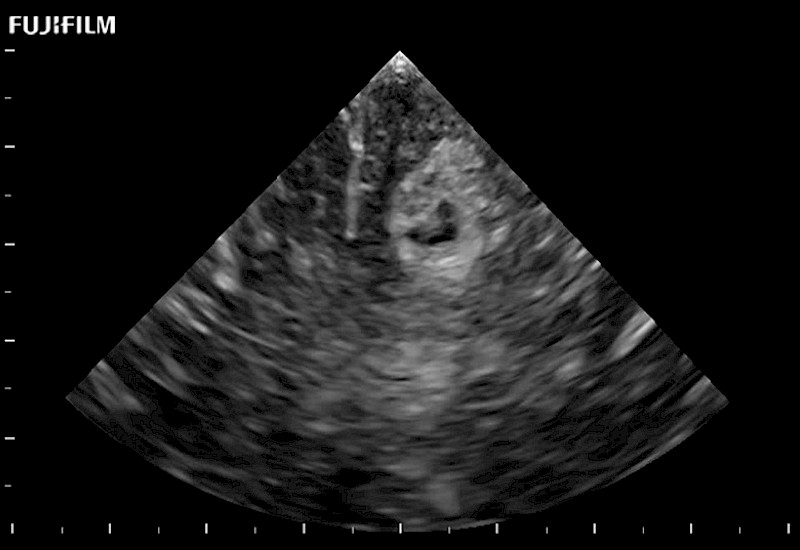

Tight curved (12mm) array transducer that is ideal for scanning during cranial guidance procedures.

Main Specifications: